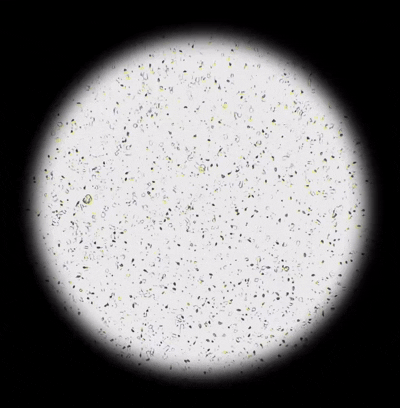

[NEW] 하고보고 정자 관찰기 2세트

집에서 간편하고 신속한 정자 상태 확인!